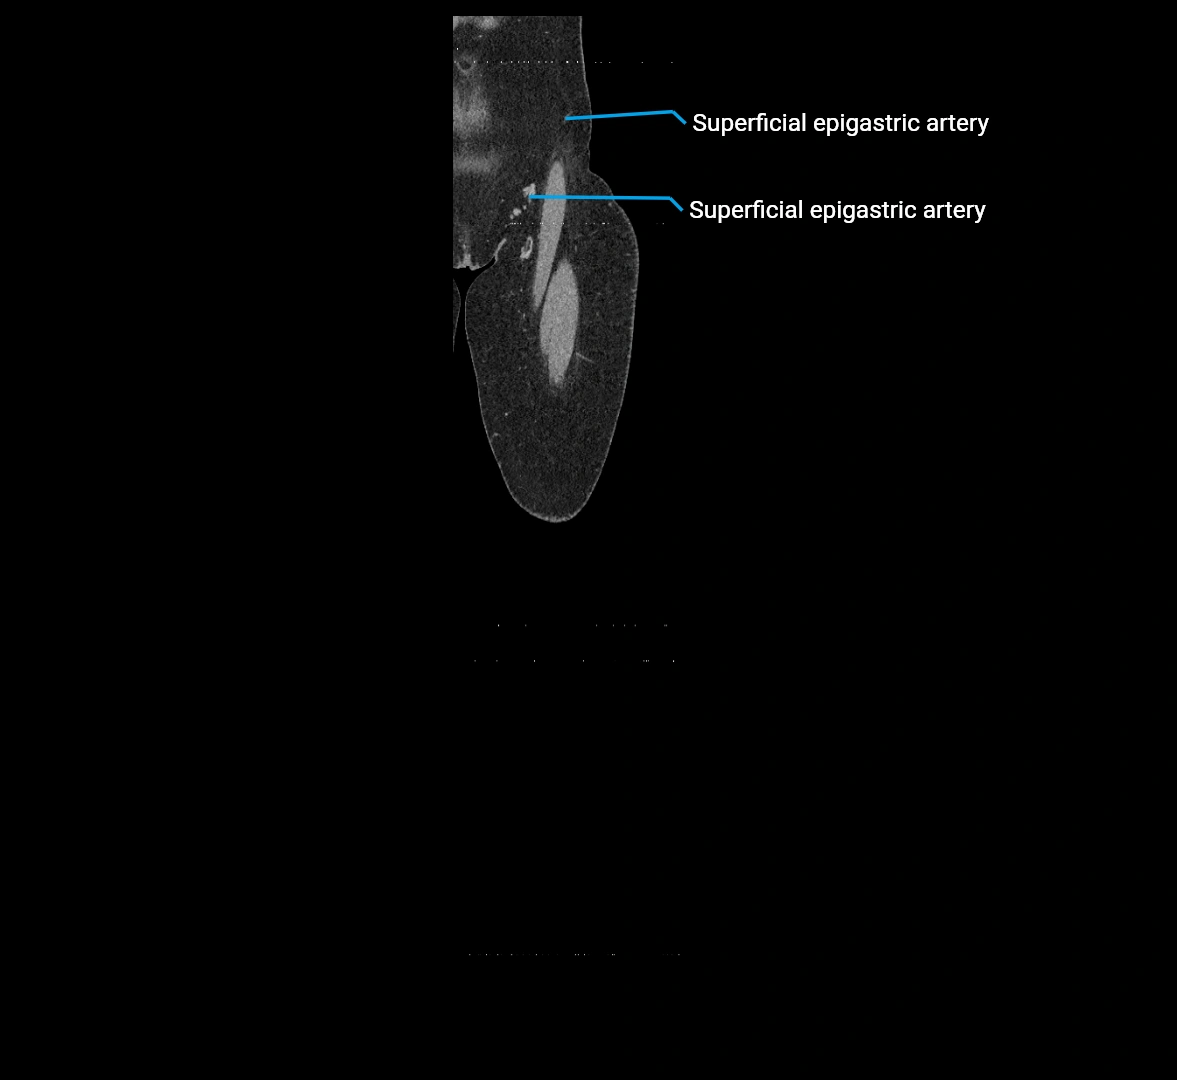

Contrast-enhanced CT (CTA):

• Gold standard for abdominal aortic imaging

• Provides excellent detail of lumen, wall, aneurysm, thrombus, and branch vessels

• Multiplanar and 3D reconstructions help in aneurysm measurement, stent graft planning, and dissection evaluation